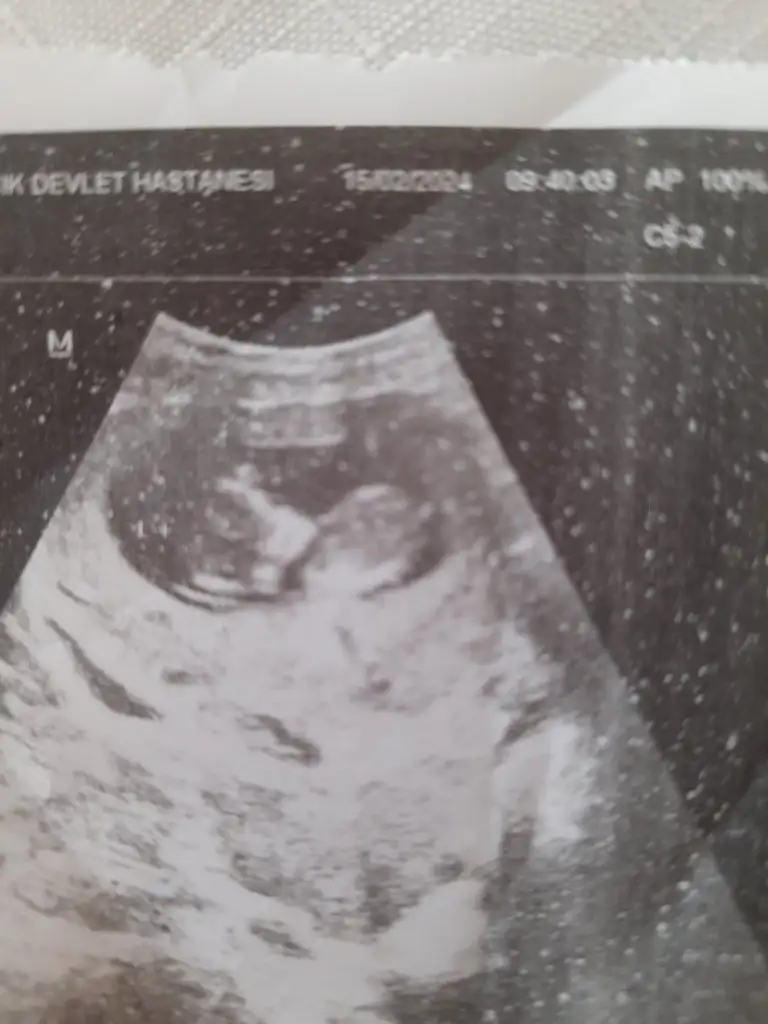

Ben de bakar bakmaz ağa gibi uzanmış bir adam gördüm, ama tamamen totomdan sallıyorumCinsiyet tahmini yapabilir misiniz nolur lütfen ?

Bi ayaklarını uzatmış ama, genelde yatarken toplu duşurta oluyorlar.Buna da bakabilir misiniz

Bence kız.